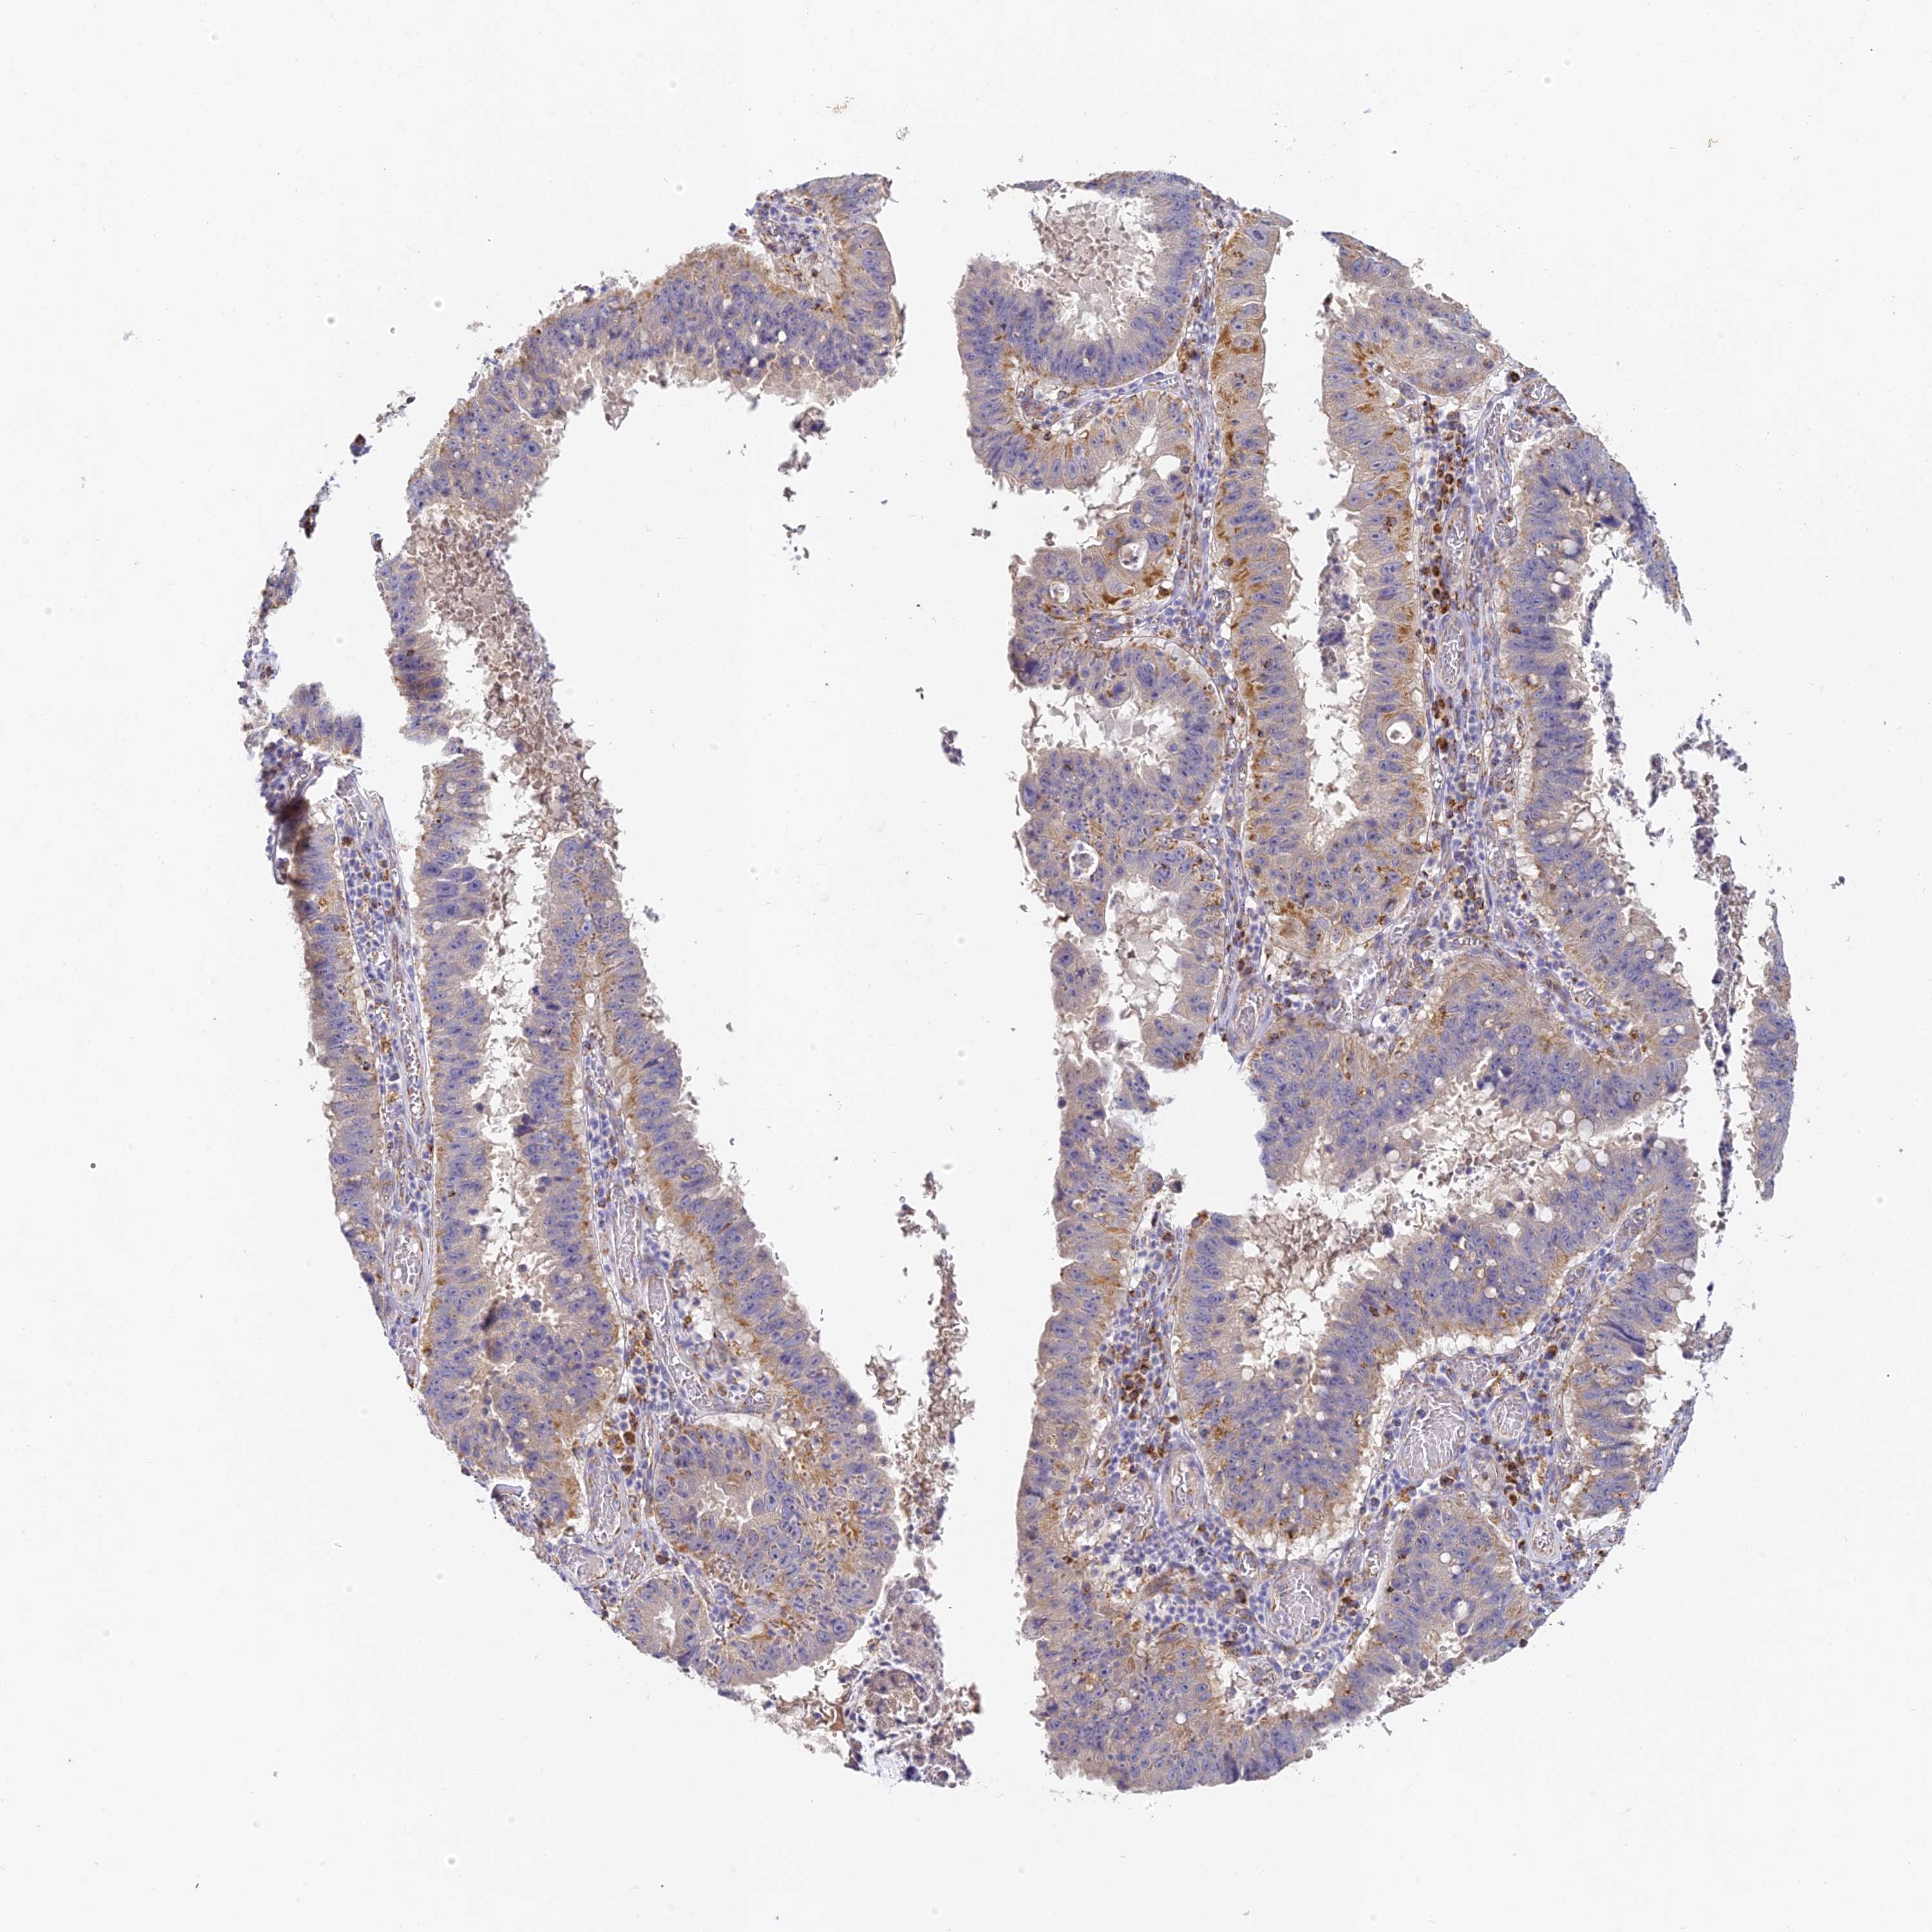

STOMACH CANCER - Protein expressioni

A mouse-over function shows sample information and annotation data. Click on an image to view it in a full screen mode. Samples can be filtered based on level of antibody staining by selecting one or several of the following categories: high, medium, low and not detected. The assay and annotation is described here.

Note that samples used for immunohistochemistry by the Human Protein Atlas do not correspond to samples in the TCGA dataset.

Antibody stainingi

Antibody staining in the annotated cell types in the current human tissue is reported as not detected, low, medium, or high, based on conventional immunohistochemistry profiling in selected tissues. This score is based on the combination of the staining intensity and fraction of stained cells.

Each image is clickable and will lead to virtual microscopy that enables deeper exploration of all samples and also displays staining intensity scores, fraction scores and subcellular localization as well as patient and tissue information for each sample.

Antibody HPA039558

Antibody HPA049033

Staining

High

Medium

Low

Not detected

Intensity

Strong

Moderate

Weak

Negative

Quantity

>75%

75%-25%

<25%

None

Location

Nuclear

Cytoplasmic/membranous

Cytoplasmic/membranous,nuclear

Adenocarcinoma, NOS

Adenocarcinoma, High grade